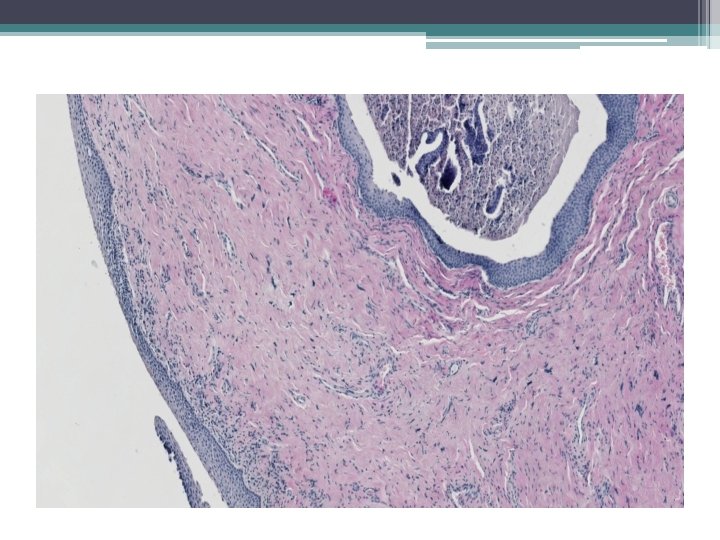

Mikro:

• Mikroskopicky: • dobře ohraničená hnízda s vrstevnatým dlaždicovým epitelem a tubuly vystlané jednou až dvěma řady kubických buněk, nebo dlaždicovými buňkami. V centru hnízd může byť přítomná nekróza s kalcifikací, nebo keratinové perly.

• Závěr: benigní polyp vaginy vznikající z ektopické prostatické tkáně (event. Skeneho žlázy, topografie není jednoznačná), jehož morfologie není zcela jednoznačná, vykazuje určité rysy tzv. tubuloskvamózního polypu, typický obraz této léze však není vyjádřen.